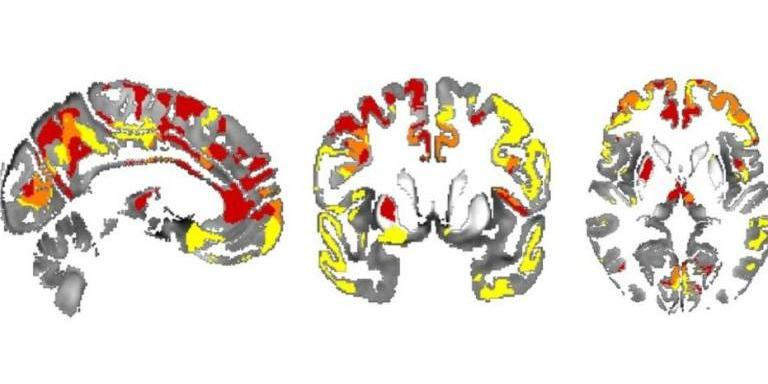

Le aree con accumulo di ferro nel cervello delle persone con Parkinson, si correlano con il rischio di declino cognitivo. (Fonte: George Thomas et al)

Nello studio attuale, i ricercatori hanno usato una nuova tecnica, chiamata 'mappatura a suscettibilità quantitativa', per mappare i livelli di ferro nel cervello in base alle scansioni MRI. Essi hanno scoperto che l'accumulo di ferro nelle regioni del cervello dell'ippocampo e del talamo, è associato a punteggi scadenti di memoria e di pensiero. Il ferro nella regione del cervello chiamata putamen è associato a punteggi scadenti nel movimento, il che suggerisce una fase più avanzata della malattia.

Nel MP, l'ippocampo e il talamo sono noti per essere associati con il pensiero e la memoria, e il putamen con il movimento, per cui i ricercatori dicono che è molto promettente che la deposizione di ferro si possa rilevare espressamente in quelle zone.